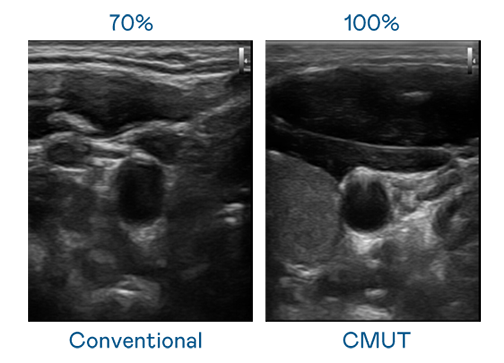

CMUT 技术是一种用电容式微机电元件来产生超音波讯号的技术。与传统 PZT 压电式技术相比,CMUT 频宽增加 30%,更宽频的超音波讯号让影像解析度大幅提升,是实现高影像品质医疗超音波扫描、促进精准医疗发展的关键技术。

大频宽带来超清晰影像

超音波影像的解析度高低,首先取决于探头能发出的讯号频宽。7790必发集团 CMUT 可提供高清晰的超音波讯号,提供高频宽、高灵敏度、影像纹理细节更高的超音波影像,协助医护人员缩短影像判读时间及利用精准的医疗影像进行诊断。